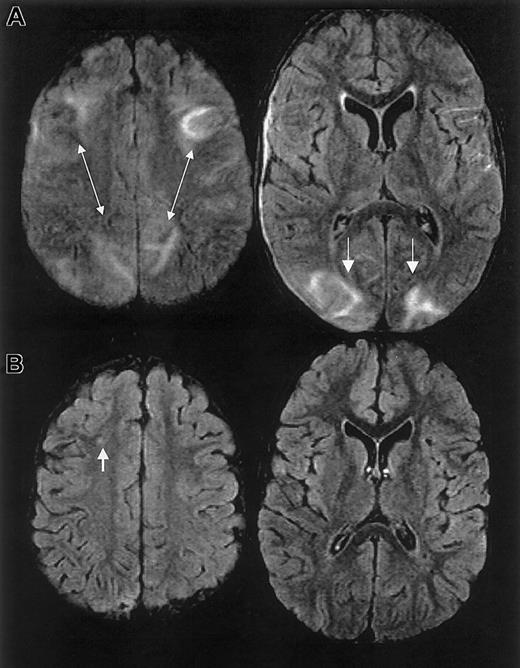

The initial clinical reading of the MRI, 1 day following endotracheal extubation, was bilateral ischemic infarcts and biparietal hemorrhages. The subsequent research reading of the initial MRI and follow-up MRI at 1 month and 15 months following discharge revealed findings consistent with RPLS complicated by hemorrhage; there was no evidence of infarction (Figure 3).

MRI findings for case 3.

(A) Extensive areas of FLAIR T2-weighted signal hyperintensity in the subcortical white matter and overlying gray matter of the posterior, frontal, and occipital lobes. Parenchymal hemorrhage was seen in the high parietal region predominantly on the patients's left. (B-C) Follow-up MRI scan 1 month and 15 months following discharge showed progressive evolution and resolution of the T2 signal hyperintensities with residual encephalomalacia in the left parietal region. These findings were consistent with reversible posterior leukoencephalopathy complicated by hemorrhage; there was no evidence of infarction.

RPLS is difficult to distinguish from acute cerebral infarcts clinically and radiographically. The distinction is important because cerebral infarction implies irreversible damage and warrants blood transfusion therapy for an indefinite period. Conversely, RPLS is potentially reversible but may require judicious hypertensive management. In this case series, 2 patients were originally diagnosed as having cerebral infarcts according to the clinical reading of the MRI, one of whom was subsequently determined to have RPLS and the other with cerebral hemorrhage. Appropriate MRI techniques and interpretation play a key role in differentiating RPLS from cerebral infarct (Figure 4). Both RPLS and cerebral infarct present with T2-weighted hyperintensities. DWIs typically show hyperintense signal in cerebral infarcts, whereas DWIs in RPLS are ambiguous because of T2 shine-through effects.8 14 Producing images of the diffusion coefficient eliminates this ambiguity.